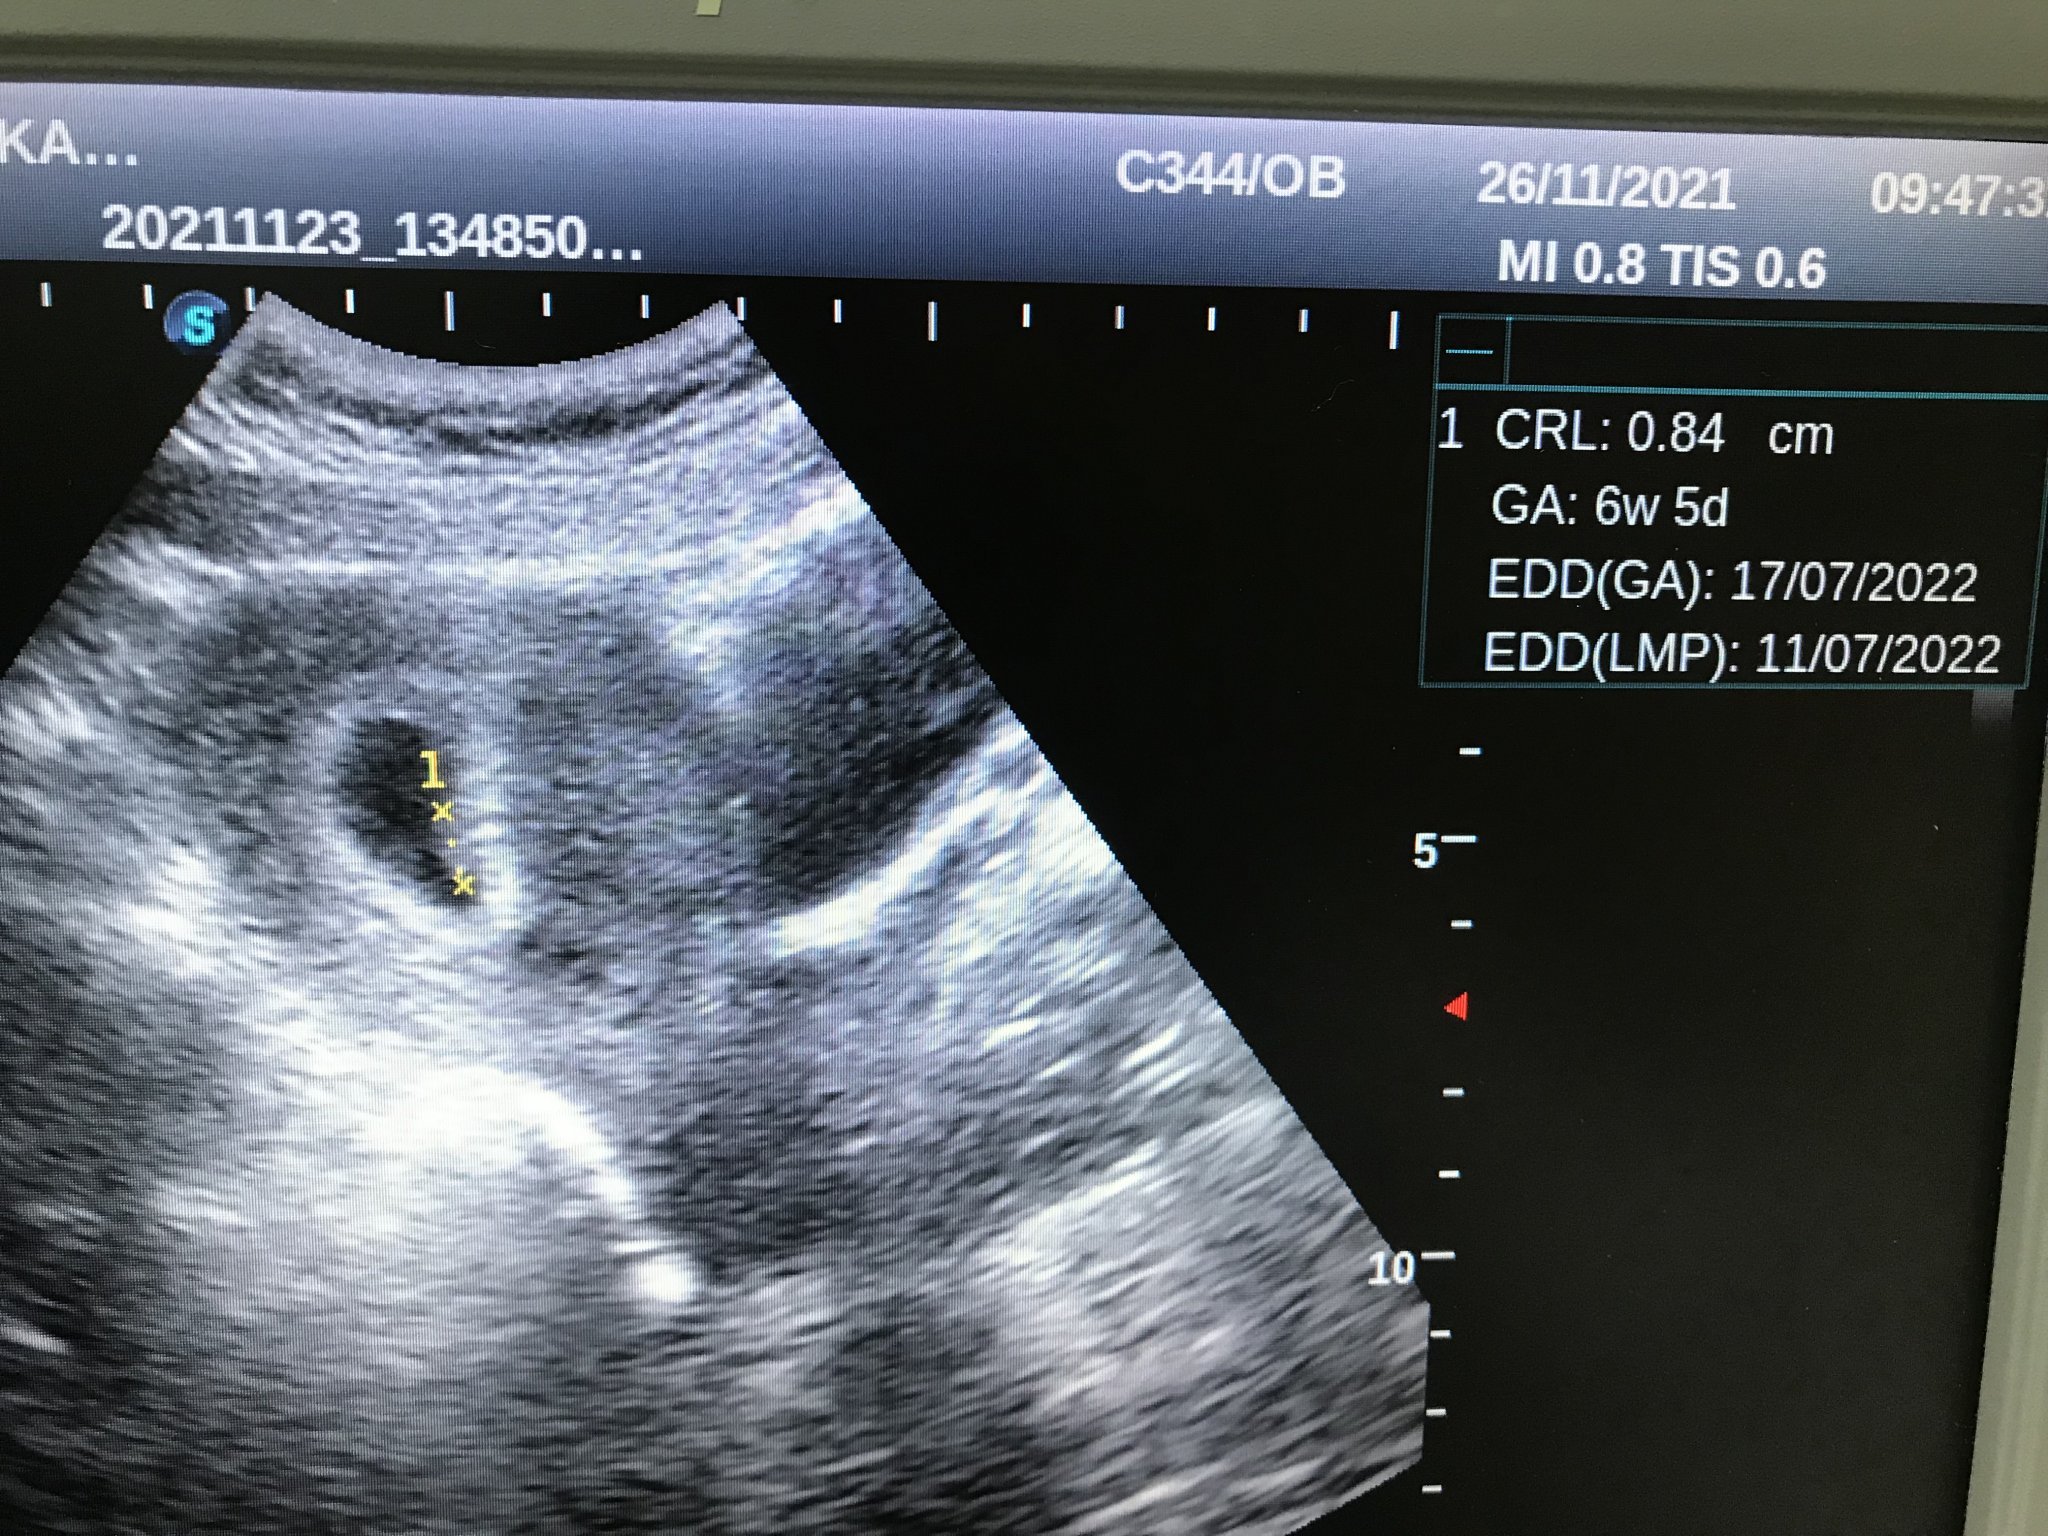

Как мога да определя датата на термина, когато цикълът ми е нередовен?